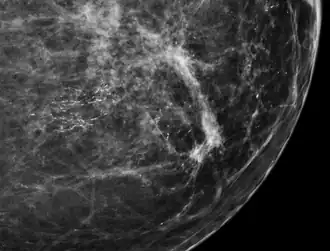

80% of cases in the United States are detected by mammography screening.[24] More definitive diagnosis is made by breast biopsy for histopathology.

-

Mammogram microcalcifications in ductal carcinoma in situ -